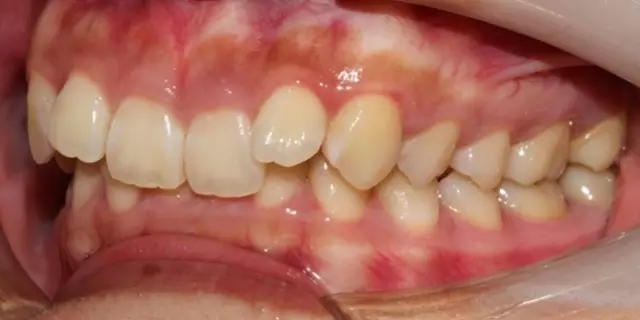

Damon 病例分享:安氏 II 類二分類露齦笑的矯治(董一磊)

治療前后對比